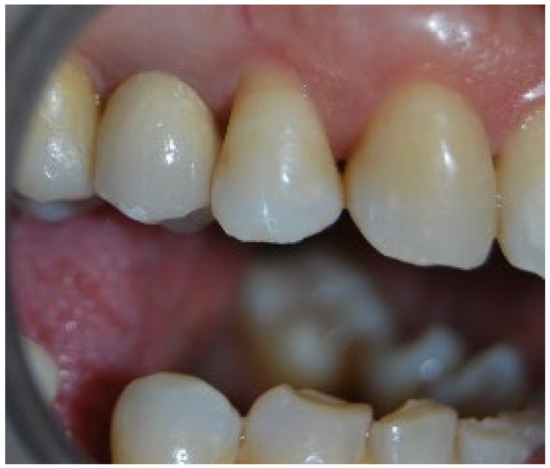

3. Results